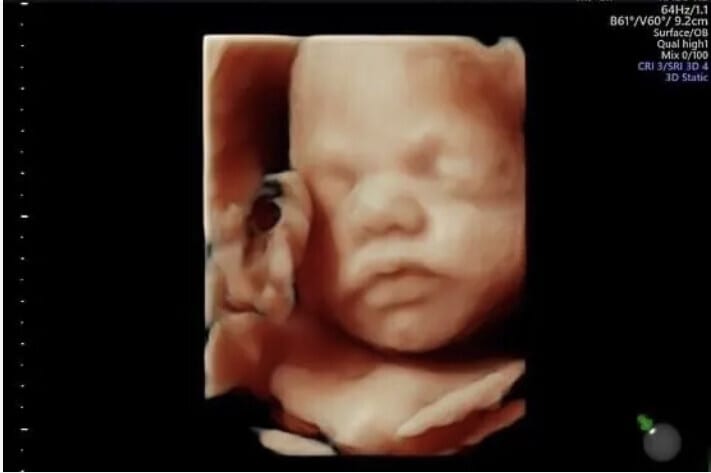

3D 4D HD Baby Scans in North London

Outstanding 4D Baby Scan | £110

You'll have the opportunity to see your baby's precious little features on a huge 75in screen, allowing you and all the family to bond with baby.

✅ Outstanding 4D Baby Scan in 'HD Live'

✅ 3D, 4D 'HD Live' Scan